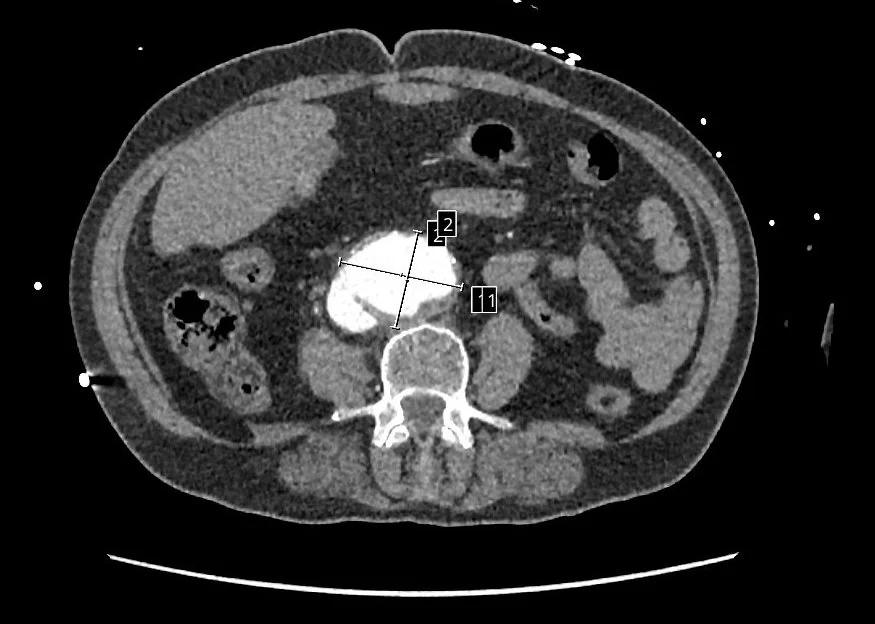

Sheperdigian says a consult and surgery with Franco Rea, MD, saved her life. The culprit, illuminated by the CT Sheperdigian ordered and shown below: an aortocaval fistula.

‍An ACF is a rare, life-threatening complication in which an abdominal aortic aneurysm erodes into the adjacent inferior vena cava, causing a direct, high-pressure shunt between the two vessels. Immediate surgery is required, as untreated cases have a near 100-percent mortality rate, according to NIH.